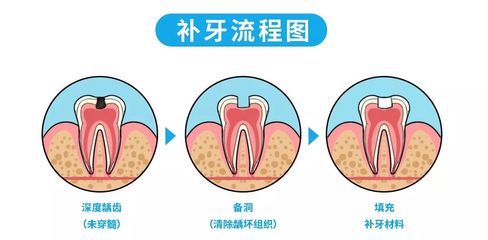

4口腔检查由专业医生进行全面的口腔检查。如果有龋齿,就要先治疗龋齿。如果有牙周炎等牙齿问题,需要治愈后才能进行正式的正畸治疗。如果有严重的牙结石,医生一般会建议洗牙。防止戴上牙套后,牙齿问题变得严重,导致正畸治疗停滞不前,反而事倍功半。5拔牙根据医生制定的计划,分批拔牙。拔牙的目的是为了给拥挤的牙齿腾出不整齐的空间。

正畸包含的范围很广,通常是指通过口腔技术手段对排列不规则、牙形异常、牙色异常的牙齿进行矫正的治疗过程。牙齿矫正的过程包括,首先,制定治疗方案。建议患者去正规医院的口腔科或者大医院的正畸科,医生会进行详细的临床检查,看牙齿排列和咬合关系,然后进行全景x线片和侧位头影片,其中部分需要进行头影测量,以确认患者有什么样的牙颌面畸形以及畸形的原因。